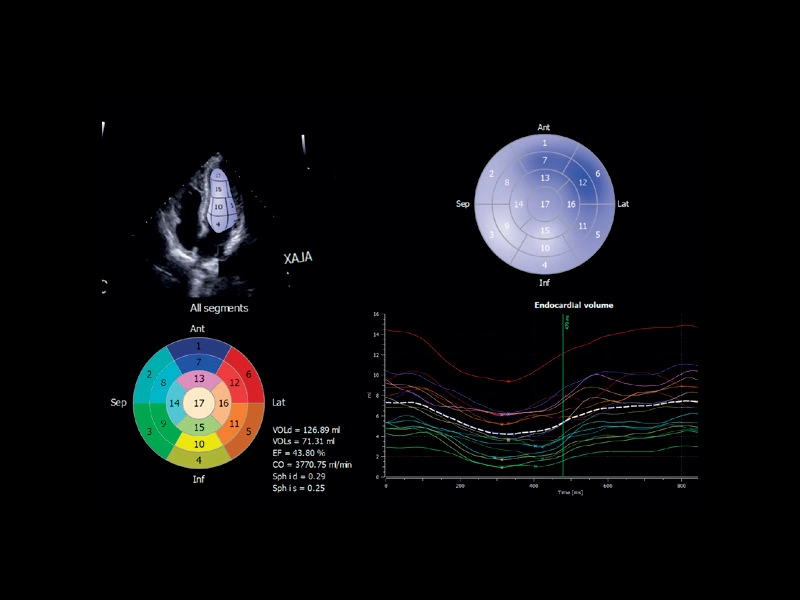

MyLab™C30 - 4d strain

MyLab™C30 - 4d strain